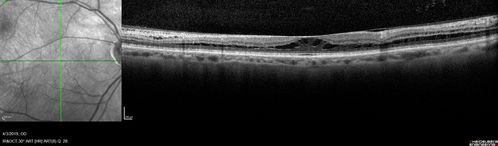

Stellate Non-heredtiary Idiopathic Foveomacular Retinoschisis (SNIFR)

77 year old man who is healthy and 6'6" tall with 20/40 vision and no complaints. OCT shows diffuse retinoschisis.